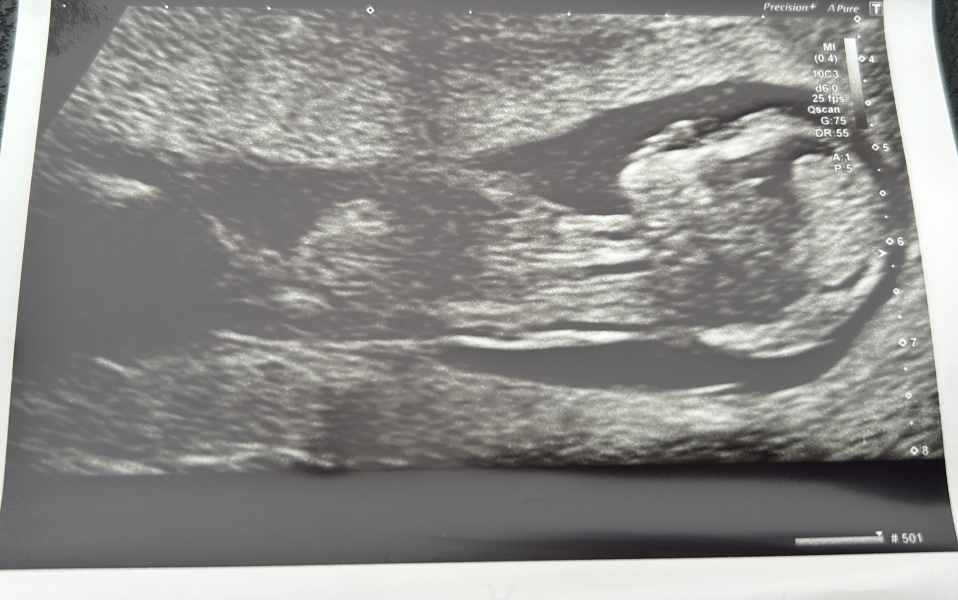

Just had our 12 week scan, and baby is measuring 2 days ahead so our new due date is the 2nd September. So crazy how much they grow in a small amount of time. All feels very real now

@Emmaev beautiful scan 😍

It's insane how much they grow between 8 weeks and 12 weeks. At 8 weeks they look like little gummy bears on scan photos and then 4 weeks later they look like actual babies!

amazing scan! 💜 I was just thinking the same @HolyMoly24 .Once they take the shape they start growing in mass.